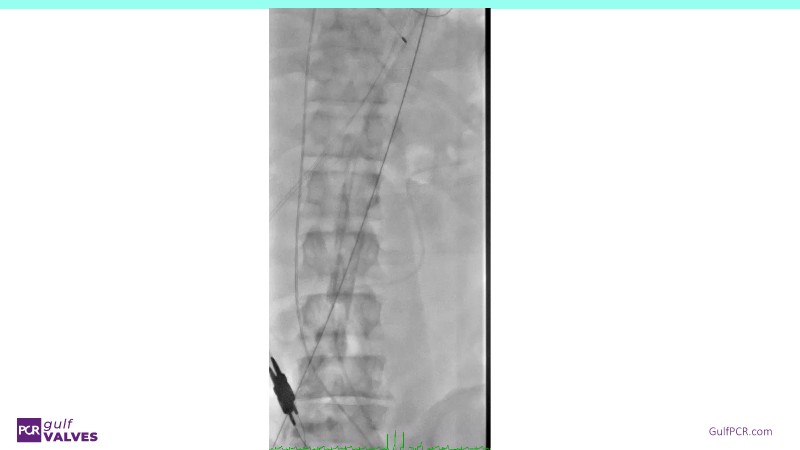

Discover a selection of cases showcasing the key features of the Navitor Valve System and its clinical applications. This session explores auxiliary access, the use of Navitor in alternative access and complex PCI, its performance in challenging peripheral anatomies, and innovative outcomes with the Vantage 30D system.